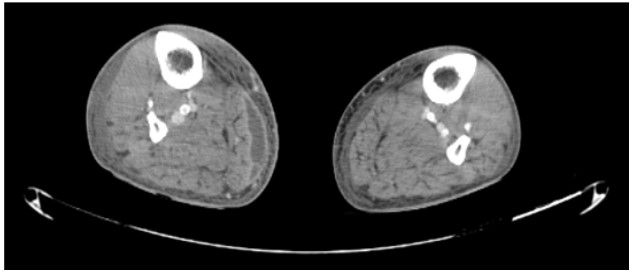

One week later, the patient recovered kidney function, and resolution of cardiovascular dysfunction occurred, enabling the cessation of vasopressor support, but progression with inflammatory signs in the entire right arm and Right Leg (RL) was noticed. CT scan revealed significant periarticular edema on the RK, soft tissues marked swelling and a 6 x 1.5 cm collection in the middle third of the RL (Figure 1). Magnetic resonance image (MRI) identified a 15 x 6 x 1.5 cm collection in the biceps brachii muscle subfascial plane (Figure 2) and an elongated set of collections, measuring up to 2 cm, involving almost the entire lateral longitudinal axis of the arm.

Figure 1: CT scan showing collection beneath the subcutaneous fat in the medial side of the middle third of the right leg measuring 6 x 1.5 cm in the axial plane (white arrow).